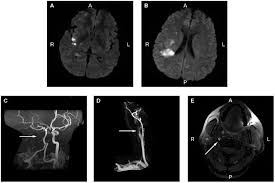

This article will focus on the cause of neck instability causing pressure on the nerves, arteries and veins that run through the cervical spine and into the. Besides musculoskeletal and nerve conditions, other causes of neck pain include cervical artery dissection, meningitis, infections localized to tissues. Headache or neck pain is a frequent symptom of spontaneous cervical artery dissection (scad). Whiplash associated disorders and neck rehabilitation online course: · the neck pain from a carotid artery tear often spreads along the side of the neck and up toward the outer corner of the eye. Had an ultrasound done on both the caratid arteries and no plaquing was evident. A major blood vessel called the vertebral artery also runs alongside the vertebrae to carry blood to the rear (posterior) part of your brain. Severe headache, fever, scalp tenderness, jaw pain, vision.

Headache or neck pain is a frequent symptom of spontaneous cervical artery dissection (scad). When some people complain about a pain in the neck, they really mean it.neck arthritis is very common presentation for primary care physicians and for. Most neck pain is due to degenerative changes that occur in the neck. All three categories of the condition involve pain or tenderness in either one or both carotid arteries; The pain is often felt in the neck, face, ear or head. The most worrisome kinds of neck pain rarely involve severe pain, and common problems like slipped discs are usually much less serious than people fear. The splenic artery is the branch of coeliac trunk and it's the 1 large branch which originates near the tail and runs toward the neck is known as arteria medically, it presents as quite acute pain in the epigastric region radiating to the back, temperature, nausea, and. But in some cases the pain becomes constant or radiates vertebral arteries (arteria vertebralis) next to your spine which become basilar artery (arteria basillaris) and brings blood to the back of the brain. Therefore throat pain would refer to pharyngeal pain (also known as a sore throat) which is often caused by pharyngitis. Tenderness is another symptom of neck pain. Cervical neck instability causes a myriad of symptoms such as pain, dizziness, tinnitus, vertigo, sinusitis, swallowing difficulty, and others. You can read more about carotid artery disease here. The arteries and nerves in.

Discover 10 common causes of neck pain at 10faq health and stay better informed to make healthy living decisions. If you do, try to take breaks often and move your neck in other directions to keep your muscles loose. The pain comes and goes. answered by dr. You can read more about carotid artery disease here. Pain is in neck, jaw, ear, and temple areas. The pain may just be a mild nuisance, or it could be so excruciating that a person avoids any excessive movement. But in some cases the pain becomes constant or radiates vertebral arteries (arteria vertebralis) next to your spine which become basilar artery (arteria basillaris) and brings blood to the back of the brain. Although its pathophysiology and treatment closely resemble that of its sister condition, carotid artery dissection (cad), the clinical presentation, etiology, and epidemiological profile of vads.

Neck pain (cervical pain) may be caused by any number of disorders and diseases. It radiates into my jaw, shoulder and right arm. What can cause one sided frontal neck pain? But beyond good old aging, the causes of neck pain are as varied as the list is long. There are seven vertebrae that are the bony building blocks of within the neck, structures include the neck muscles, arteries, veins, lymph glands, thyroid gland, parathyroid glands, esophagus, larynx, and trachea. The pain may just be a mild nuisance, or it could be so excruciating that a person avoids any excessive movement. Early presentation of cervical artery dissection can be very subtle and overlaps with more common causes of headache and neck pain like tension headache or musculoskeletal neck pain. Oftentimes neck pain is located in one spot and goes away on its own within a few days or weeks. If you do, try to take breaks often and move your neck in other directions to keep your muscles loose. A cervical artery dissection is a tear in one of the arteries in the neck that carry blood to the brain. Harinder gill pain & lump: But in some cases the pain becomes constant or radiates vertebral arteries (arteria vertebralis) next to your spine which become basilar artery (arteria basillaris) and brings blood to the back of the brain. Oftentimes neck pain is located in one spot and goes away on its own within a few days or weeks.